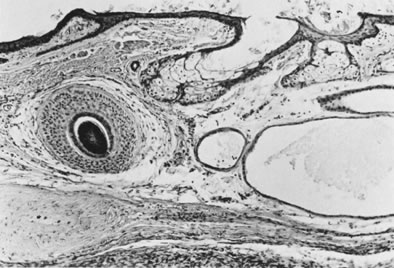

DERMOID CYST.

The mature cystic teratoma is almost always a dermoid cyst lined by skin with its appendages (Figs. 28 and 29), although this type of lining may alternate with respiratory epithelium or mature glial tissue.57 Rarely, a mature cystic teratoma is lined entirely by one or the other of those tissue types. Most dermoid cysts contain mesodermal and endodermal, as well as ectodermal derivatives, and almost every type of tissue has been identified in individual cases. Occasional, otherwise typical, dermoid cysts contain microscopic foci of immature tissue, which merits only a comment and not a diagnosis of immature teratoma.58

Fig. 28. Sectioned surface of dermoid cyst.

Fig. 29. Dermoid cyst with hair follicle ( left ), sebaceous glands, and sweat glands (magnification, ×80).(Serov SF, Scully RE, Sobin LJ: Histological Typing of Ovarian Tumours. Geneva, World Health Organization, 1973.)